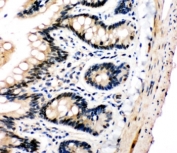

IHC-P: PLK2 antibody testing of human lung cancer tissue. HIER: steam section in pH6 citrate buffer for 20 min and allow to cool prior to staining.